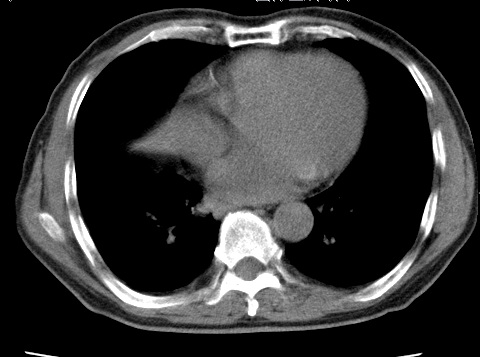

考虑右肺中叶不张,请大家发表意见

右肺中叶不张、肺门轮廓增大,占位不除外;建议增强,必要时支气管镜详查。

右肺中叶支气管闭塞,中叶肺不张,右侧肺门见肿块影。中心型肺癌的可能大。建议支气管镜检查。

考虑右肺中叶中央型肺癌并右肺中叶肺不张;建议:行纤支镜检查。

右肺门旁类圆形肿块影,右肺中叶不张,建议纤支镜检查。

中央型肺癌并不张

1右肺门旁类圆形肿块影,右肺中叶不张,建议纤支镜检查